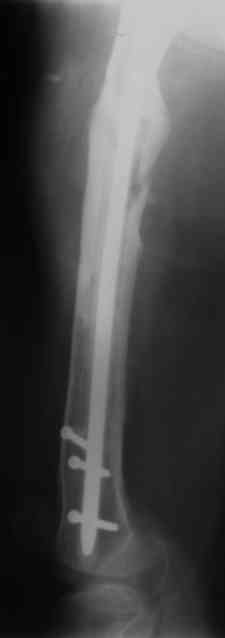

В настоящее время наш пациент ( см. http://weborto.net/forum/1177351385/) ходит с одним костылем. У него периодически открывается свищ на задне-наружной поверхности бедра с умеренным серозно-гнойным отделяемым. Температура тела и анализы нормальные. На рентгенограммах имеются признаки консолидации ложного сустава.

Иллюстрации:

1, 2, 3, 4 - рентгенограммы бедра от 8 августа этого года (через четыре месяца после операции);